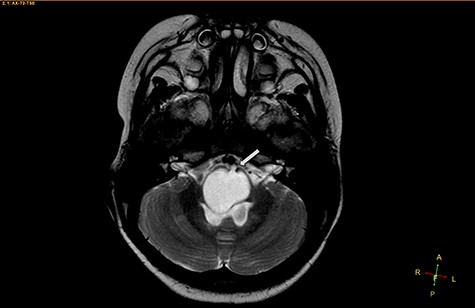

A 3-year-old male, who suffered from a sudden, tonic–clonic seizure, followed by a short period of unconsciousness, was instantly transported to Children’s Hospital 2. The patient’s medical history was normal. No neurological deficits were detected during the clinical assessment, and laboratory tests and electroencephalography were within acceptable ranges. The clinician performed a brain magnetic resonance imaging (MRI) scan, with contrast agent. No lesions were recognized in the supratentorial structures. A clear boundary cystic mass (27 × 25 × 26 mm3) was located in the medulla oblongata, without perilesional vasogenic edema. Hydrocephalus was not observed. The signal intensity of the mass was low on the sagittal T1-weighted image (Fig. 1) and high on the axial T2-weighted image (Fig. 2). On coronal fluid-attenuated inversion recovery imaging, the mass was isointense relative to the parenchyma, but the intensity was higher than that of cerebrospinal fluid (CSF, Fig. 3). On susceptibility-weighted imaging, no indicators of hemorrhage or ossification were observed within the mass. The mass was partially hyperintense on diffusion-weighted imaging (DWI) and slightly hypointense on the apparent diffusion coefficient (ADC) map. The mean ADC values of the parenchyma, mass and CSF were 0.71, 1.3 and 1.59 × 10−3 mm2/s, respectively (Fig. 4). On T1-weighted imaging, with contrast enhancement, the thin wall of the mass was very slightly enhanced, and we observed a tiny nodule inside the mass that was strongly enhanced (Fig. 5). With a provisional diagnosis of pilocytic astrocytoma, the patient underwent surgery to completely eradicate the tumor. Eventually, the histopathological result revealed a typical EC (Fig. 6). The postoperative period was uneventful, and the patient was discharged after 2 weeks.

Axial T2-weighted image, showing a hyperintense, cystic mass inside the medulla oblongata. Exceptionally, the lesion appears to progress from extra-axial to intraparenchymal (arrow).